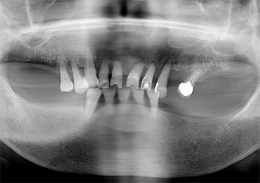

下顎のALL-ON-4①(下の歯のオールオンフォー)

- 主訴

- もともと入っているインプラントの周りが腫れ、残りの歯も動いているので力が入らない

- 治療内容

- 下顎右側に以前埋入したインプラントの撤去を行い、歯周病の進行が著しかった残存歯の抜歯を行うと同時にインプラントの埋入を行い、当日仮歯を装着した

- 治療費用

- 下顎ALL-ON-4:4,000,000円(税別)

- 治療期間

- 6ヶ月